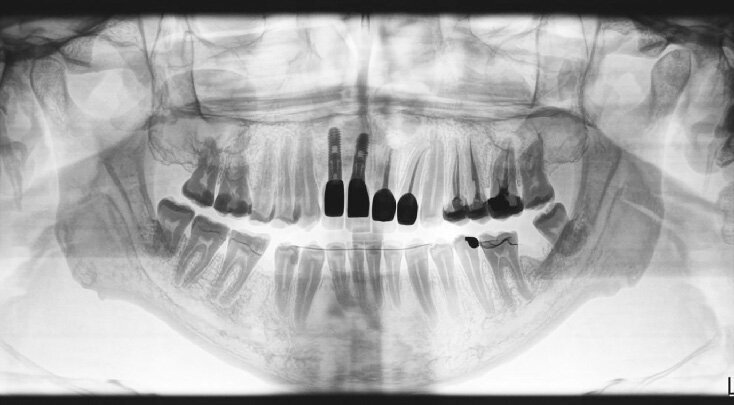

Figure 4: Preoperative view showing vertical and horizontal bone loss.

Figure 18: OPG showing the final cemented restorations no 7 and 8.

Figure 20: Periapical X-ray showing a 1.5 cm radiolucent lesion extending on apexes of teeth no 7 and 8 , note the lateral perforation on tooth no 7.

After removal of the bridge an extended bone loss was found. (Fig.2, 3). X-rays and CAT views were taken for the region. The amount of bone loss was extended which was an indication for autologous bone graft. A PRF associated bovine bone technique was planned. A linear incision with mucoperiosteal flap elevation was conducted. The adjacent teeth showed also bone loss (Fig.4).

A 33 years-old male patient was visiting our clinic to replace missing teeth no 7 and 8. He was medically fit and mentioned that his teeth were lost due to car accident few years back. Intraoral examination shows absence of space for implant placement and restoration, orthodontic treatment was conducted for 18 sessions followed by surgical implant placement after stabilization of the occlusion. Following the restoration of the space, the amount of horizontal bone loss was evident both clinically and on CAT examinations (Fig.10, 11). A linear incision with mucoperiosteal flap elevation were conducted, the amount of horizontal bone loss was advanced (Fig. 12), which was an indication for autologous bone graft, patient refused to undergo an invasive surgery so PRF associated bovine bone was planned in the area. Blood withdrawal and centrifugation were done with preparation of both L-PRF membranes and sticky bone (bovine bone associated PRF) (Fig.13, 14,15). The combination was placed on the host bone deficiency and covered by a first layer of L-PRF membranes in order to stabilize the graft and insure hemostasis, the second layer of L-PRF membranes covered the cross linked collagen membrane placed in the same area and covering the first entity (Fig.16).

A 38 years-old female patient came to our clinic with swelling upper anterior area, she was medically fit with no health problems. The patient underwent an orthodontic treatment for 2 years and was about to remove it and place retainer. Intraoral examination showed swelling apical area of tooth no 7. The periapical x-ray and CAT view revealed a lateral perforation on the same mentioned tooth with a well circumscribed radiolucency in apical area (Fig.20, 21). Pain on percussion and slight mobility were noted. A surgical enucleation and extraction of tooth no 7 were conducted (Fig.22, 23, 24). 3 months postoperative CAT view shows an advanced horizontal bone loss with no recurrence of lesion in the area (Fig. 26), clinically after reflection of mucoperiosteal flap, the situation confirmed the CAT image (Fig.25) , the case was planned for PRF -associated bovine bone technique replacing the aggressive autologous bone graft procedure. After collection of PRF from patient blood culture, a first layer of L-PRF covering the bovine bone associated PRF complex (sticky bone) was done (Fig.27). The second layer of L-PRF came to cover the cross-linked collagen membrane (Fig. 28).